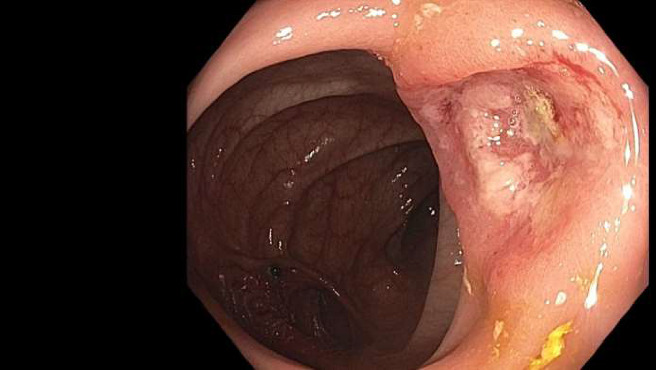

Colorectal cancer (CRC) continues to be a significant global health issue contributing to a high mortality rate. Despite advancements in treatment, the risk of recurrence remains due to inherent mutations and the rapid turnover of intestinal mucosa. We present an exceptionally rare case of CRC metastasis to the duodenum in a 42-year-old female who has been compliant with postsurgical surveillance. Despite previous negative surveillance results, elevated CEA levels and a 3-cm mesenteric mass were detected, raising concerns for carcinoma, which was later confirmed by biopsy. The tumor board deemed her ineligible for surgery due to vascular involvement, leading to palliative care and an attempt at neoadjuvant therapy. Vigilant monitoring is crucial for early detection and intervention.